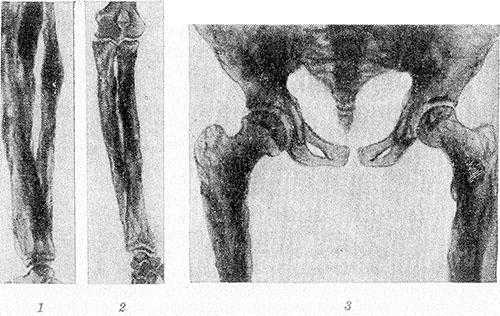

Рис. 2. Рентгенограммы костей голени (1), предплечья (2), таза и верхней трети бедер (3) больного системным гиперостозом: длинные трубчатые кости цилиндрически и булавовидно утолщены, корковый слой неплотный, резко утолщенный, имеет неравномерную пятнистую структуру с неровными контурами; кости таза утолщены.

Рентгенологически определяется симметричный гиперостоз трубчатых костей скелета. Пораженные кости громоздки, их диафизы утолщены в 2—3 раза, костно-мозговой канал равномерно сужен, но никогда не исчезает полностью. Эпифизы не изменены. Корковый слой значительно утолщен кнаружи и кнутри, с явлениями остеосклероза, но структура его не нарушена. Рисунок губчатого вещества изменен — костные балки грубы, толсты, плотны и обрывисты (рис. 2). В детском возрасте структурный рисунок может быть неравномерным, иметь рассеянный крупнопятнистый очаговый характер.